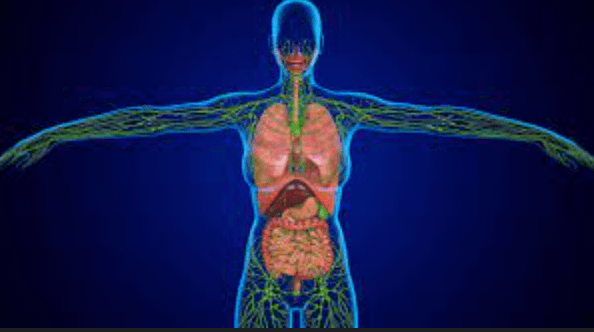

Allows exchange of oxygen and carbon dioxide.

What is the respiratory system?

Collects, interprets, and sends information regarding the body and its environment via electrical signals.

What is the nervous system?

Controls the body’s activities by utilizing chemical messengers known as hormones that travel in the blood.

What is the endocrine system?

Our body's 'sewerage system'. It maintains fluid levels in our body tissues by removing all fluids that leak out of our blood vessels.

What is the lymphatic system?